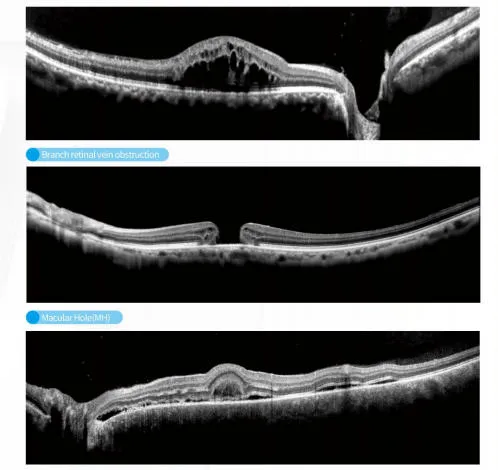

OCT Imaging Analysis

OCT Structural Scan

The C800 incorporates automatic eye-tracking, SLO scanning, and multi-mode tomographic imaging, ensuring stable visualization even for patients with difficulty maintaining fixation. Advanced choroidal thickness measurement and macular mapping support precise monitoring for myopia control, diabetic retinopathy, glaucoma, and age-related macular degeneration.

It is ideal for monitoring and detecting myopia, diabetic retinopathy, glaucoma, and age-related macular degeneration through advanced choroidal and macular mapping.